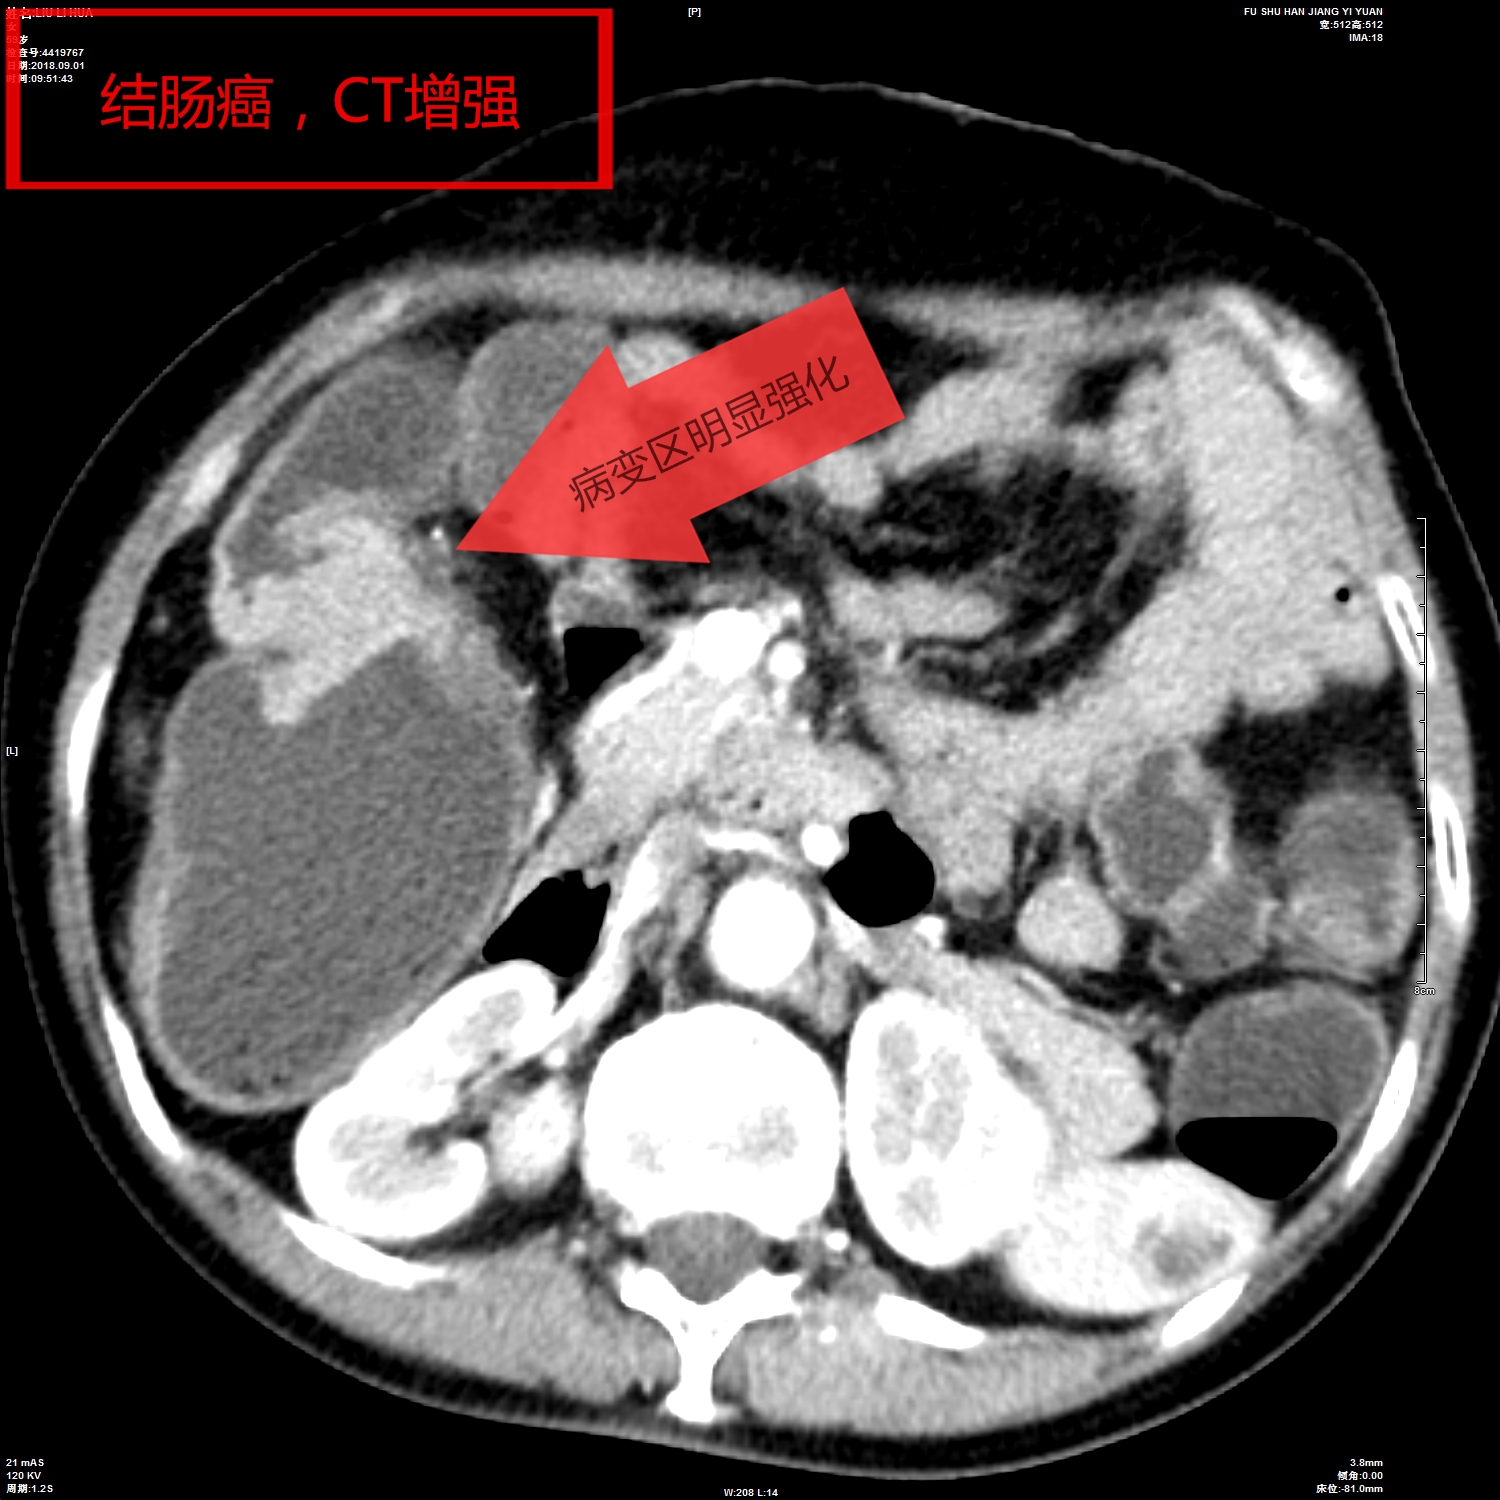

我院影像科从2018年开始,利用CT、MR分辨率高、成像方法多的特点,开展胃肠快速充盈低张CT、MR检查技术,通过多序列、多窗位、多方位检查,对肠壁、及其腔内腔外病变连续观察,取得了很好的检查诊断效果。检查技术成熟安全、无创,确诊了多例胃癌、胃息肉、结肠癌、肠先天性发育旋转不良等胃肠道疾病,并对肿瘤的转移及周围结构进行评估,为患者进一步综合治疗,打下了坚实的基础。

胶囊内镜检查具有移动的不可控性,常规消化道纤维内镜存在视野局限、有创,通过障碍无法评估腔外解剖与病变,对通过障碍的病灶仅能显示病变近端,然而胃肠道快速充盈低张影像检查技术具有无创、反复观察、定位准确的优势。它可通过充分的肠道准备,虚拟内镜及多方位重建,可从任意角度和方式对病灶进行观察,并能从狭窄、梗阻处两端观察肠腔的解剖和病变,可靠的显示了病变部位和范围,同时提供腔内外的情况并能对淋巴转移、血管癌栓、远处转移进行评估。

影像图片(二)